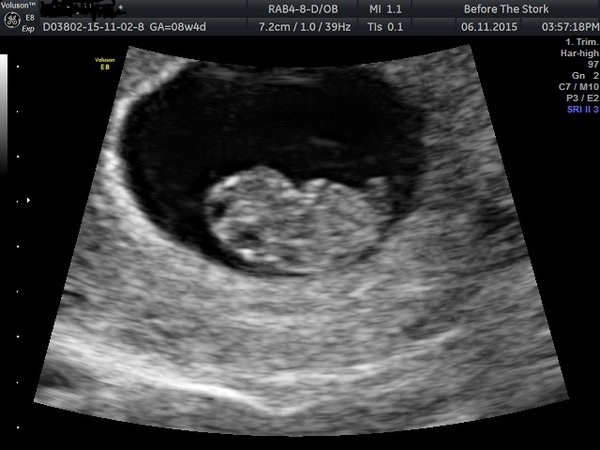

I had to move my scan appointment forward to yesterday afternoon as at lunch time yesterday I started bleeding bright red blood. Thank god all seems well and baby looks fine, heart beating and has grown from 16mm on Monday to 19.5mm yesterday. She could not find any cause for my bleed and there was no blood near to the baby. And the bleeding seems to have stopped now. Really thought that was it, so very relieved now!

Also baby looks even bigger and I think I can see a leg on this picture!

Lovely scan picture violet how far along are you?

Violet lovely scan picture Smile

Lovely scan violet, I'm so pleased everything is ok.

Miracles I'm 8+5 today.